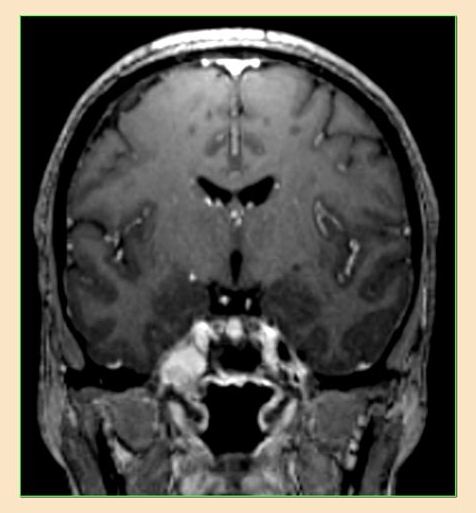

Brain Tumor-trigeminal schwannoma-microsurgery-dr Suresh ...

These are benign tumors arise from trigeminal nerve and cause head ache,facial pain,giddiness,tinnitus,reduced hearing,difficulty in chewing,swaying while walking,double vision,MRI/CT SCAN are dignostic,microsurgical excision will cure the condition.these are also commonly associated ... View Video